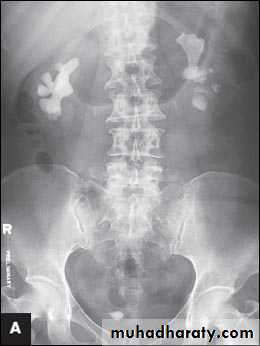

Regarding the KUB + IVU films

a. Must looks carefully to KUB film for any radio opaque shadow ( so it is stone )important pitfall in stage horn calculous the calcified large stone take the shape renal pelvis could be unilateral or bilateral so not to be confused with hydronephrosis by looking to the pelvis in which cystogram is not seen

These are stage horn calculus